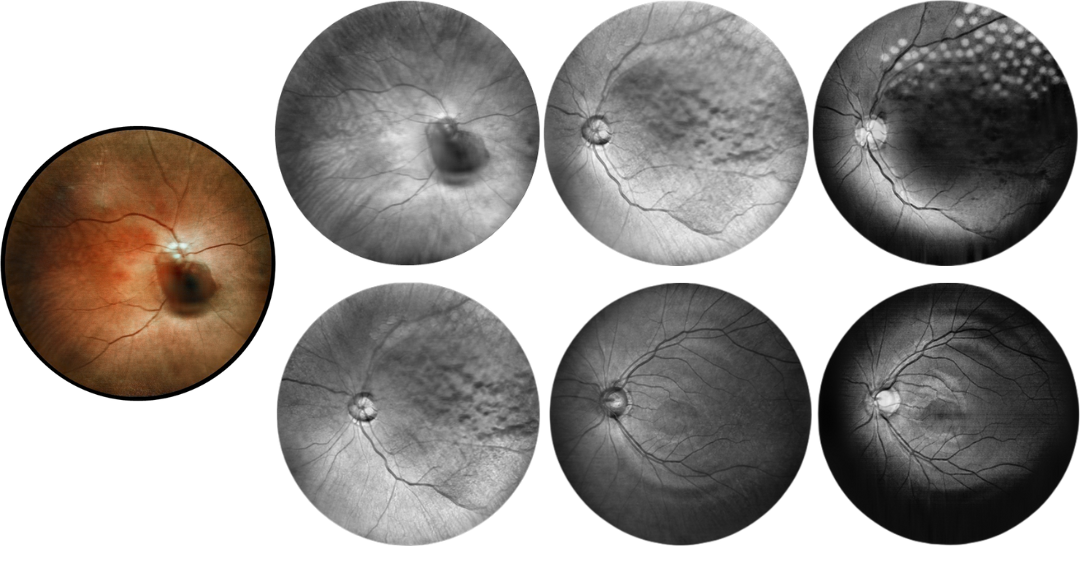

Retina Examination Under Cataracts

Examining fundus diseases through cataracts is a crucial topic in ophthalmology. Traditional fundus cameras cannot see through cataracts to capture fundus conditions. However, our DF600 scanning laser ophthalmoscope can penetrate moderate cataracts, providing a glimpse into the fundus and offering greater convenience for fundus examinations in patients with cataracts.

Fundus Cases Display

Our SLO makes fundus examination easier for you, capturing ultra-clear and wide-angle images of the retina and choroid, and then synthesizing color fundus images to present a rich picture of the fundus status.

Diabetic retinopathy: post photocoagulation

Diabetic retinopathy: bleeding and microvascular lesions

Diabetic retinopathy: post photocoagulation

Diabetic retinopathy: bleeding, exudation, and post-photocoagulation

Diabetic retinopathy: bleeding

Diabetic retinopathy: bleeding and exudation

Diabetic retinopathy: vascular abnormalities, bleeding spots, and post-photocoagulation

Diabetic retinopathy: bleeding, exudation and choroidal vascular abnormalities

High blood pressure, venous obstruction, and bleeding